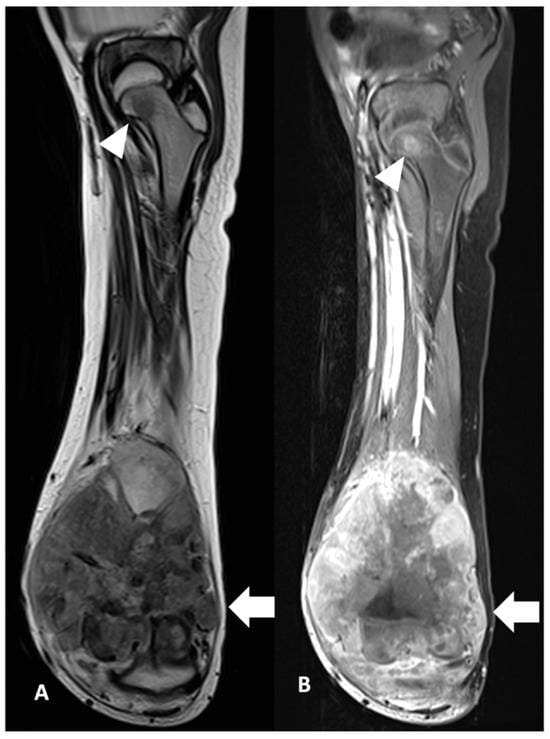

2.2. Analysis and Definition of Study Variable